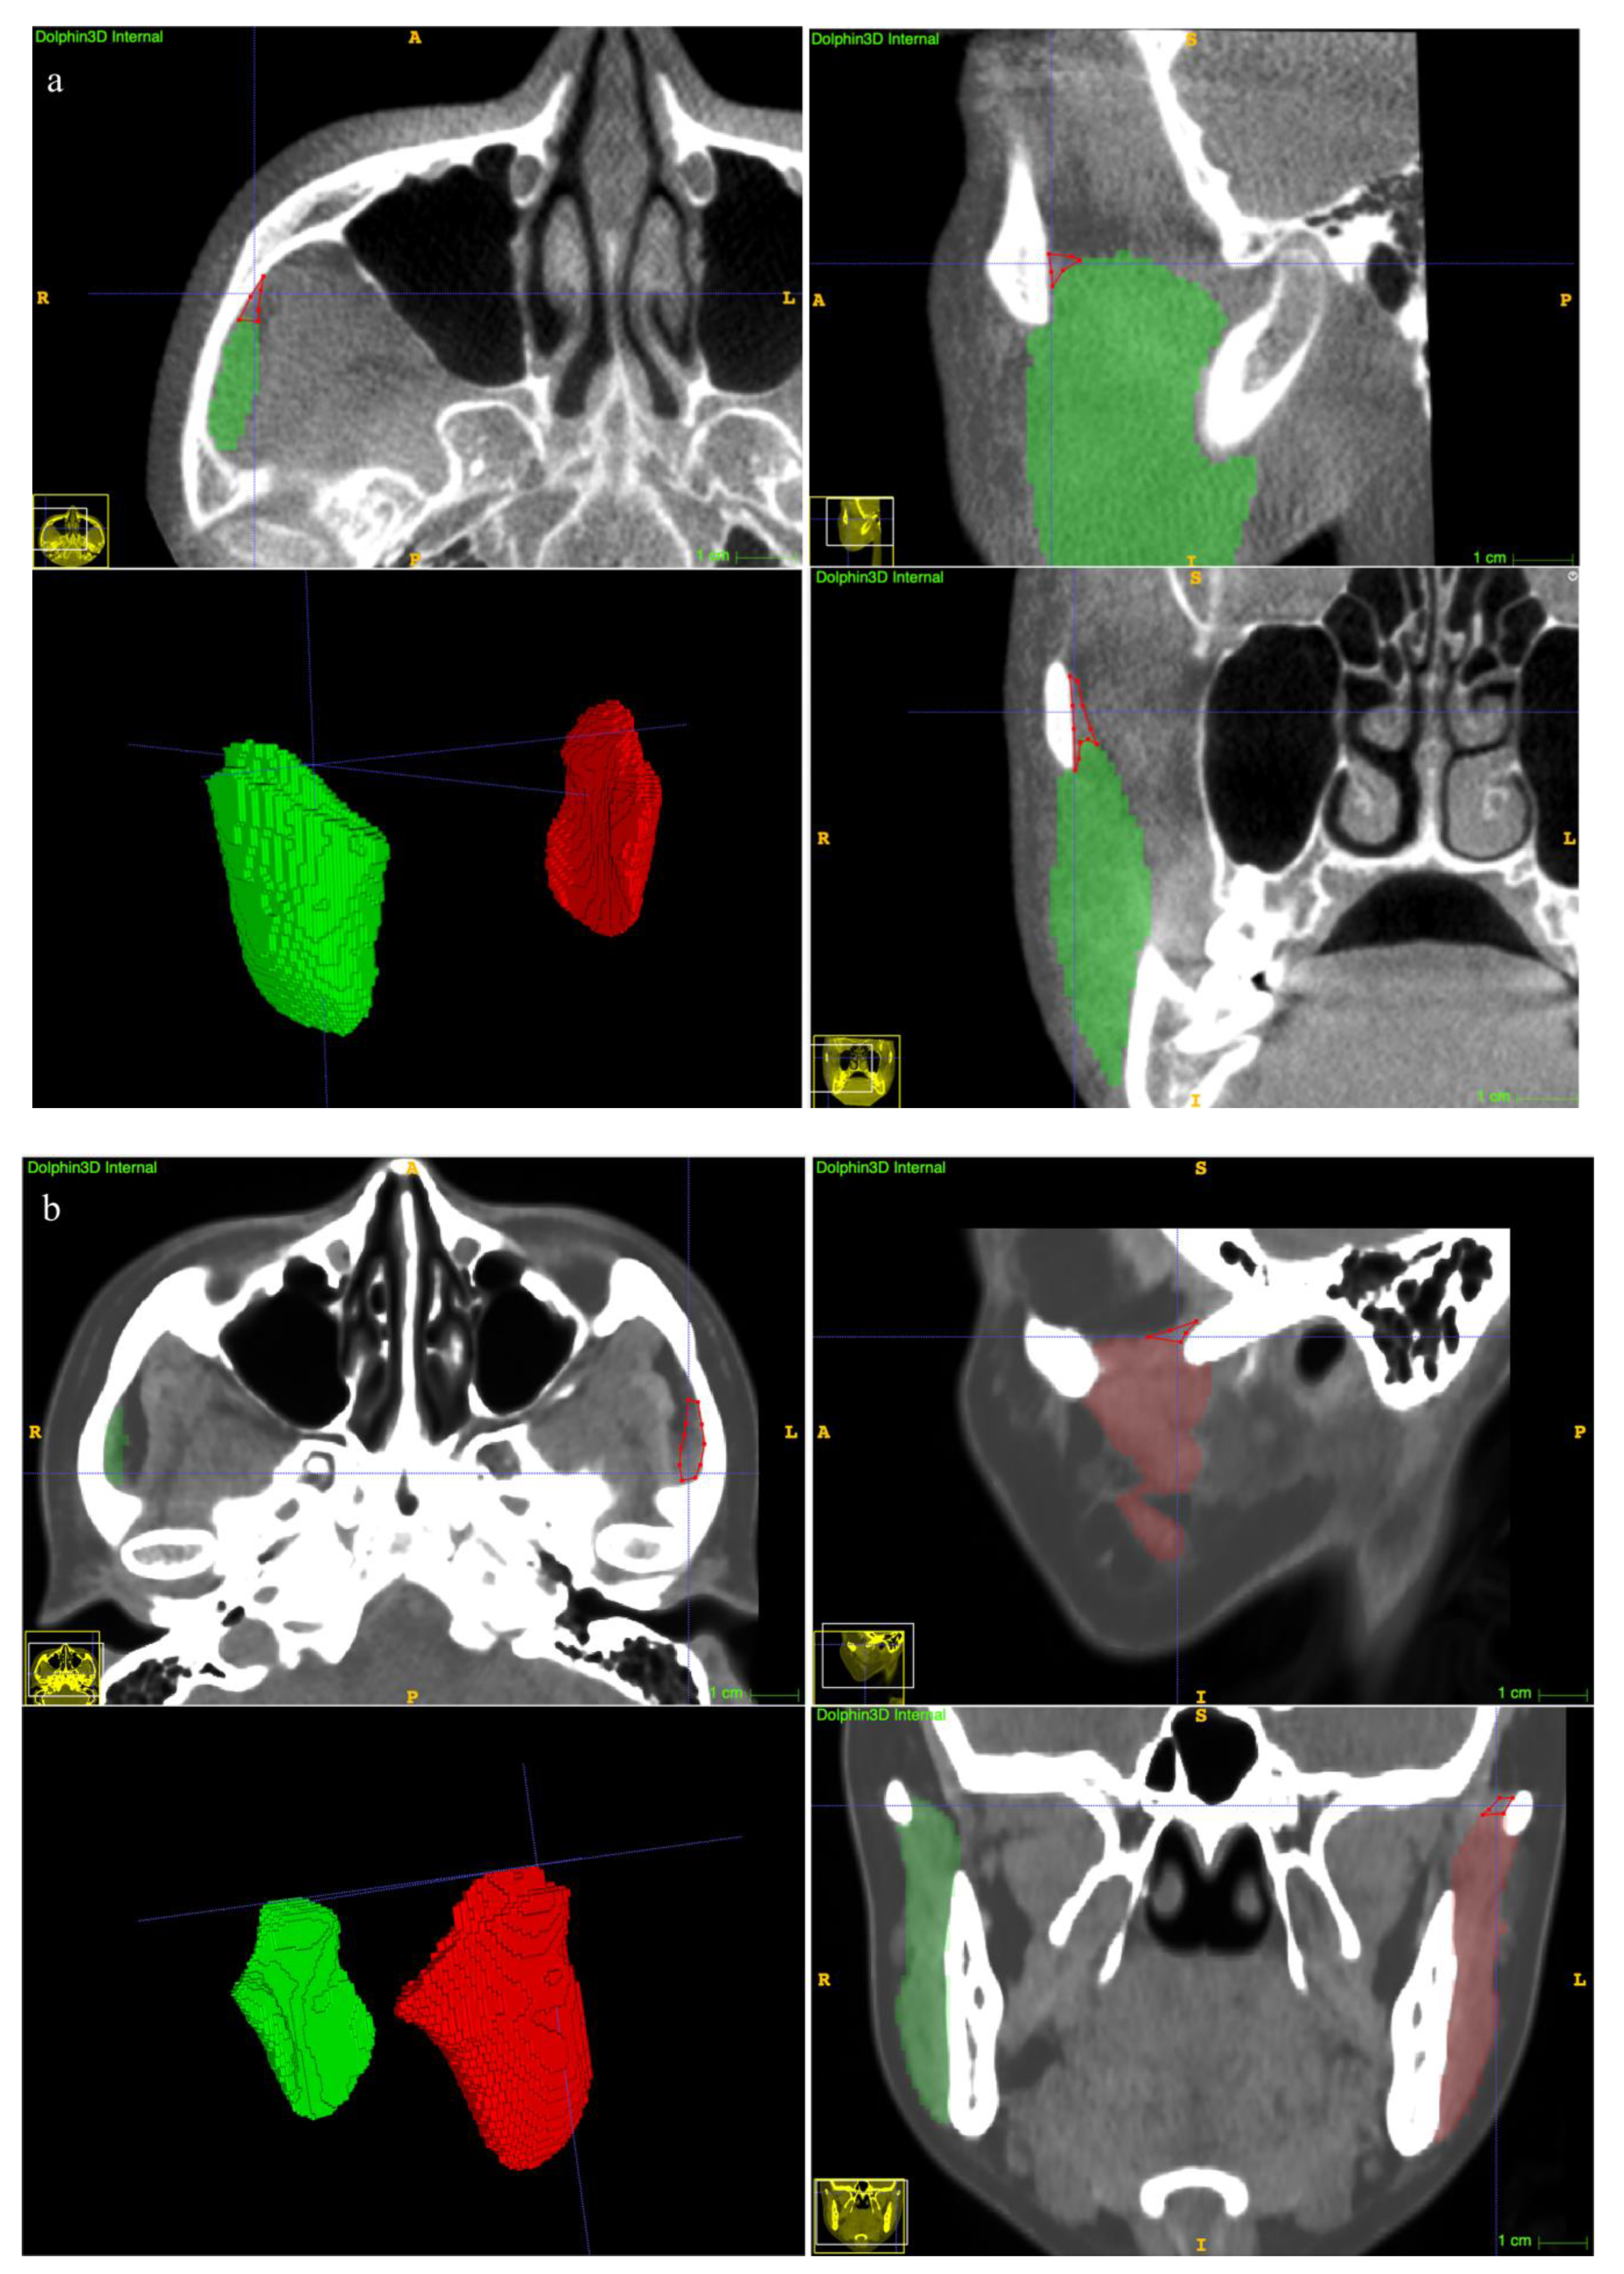

The clinical suitability results are summarized in Table 5. The manual revision was mainly focused on the superior extents (examples depicted in Figure 7a,b). A mean revision fraction of 0.52 ± 0.44% was needed for both CBCT and CT auto-segmentations, and the revision fraction ranged from 0.25% to 0.72% for each side of the MM. The mean DSCMean was 99.84 ± 0.14%, and the mean aHD was 0.92 ± 0.88 mm. SD, standard deviation.

With regard to the clinical suitability of the model, minor manual modifications for both the CBCT and CT auto-segmentation results were needed in this study (the mean manual revision fraction was 0.52 ± 0.44%, Table 2). A previous study reported a mean 22.86% of case revisions [18], suggesting an obvious improvement in terms of accuracy of our proposed method. Refinement was focused on the superior extents (Figure 7a,b). The explanation was that visualization of the MM superior ligament is poor [1], and the model threshold settings affect the identification results.

Figure 7. Examples of undersegmentation of the automatic model on the superior extent of the MM. The red polygon shows the undersegmented area. (a) CBCT segmentation results. (b) CT segmentation results.